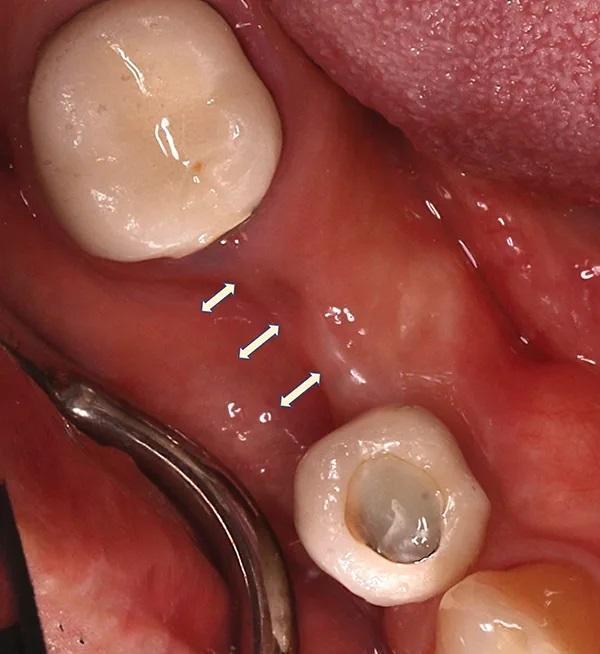

Пациент приходил для осмотра через 1, 2, 4, 6 (снятие швов), 8, 12, 16 и 24 недели (фото 10). Пациент четко соблюдал рекомендации, поэтому отлично контролировал образование зубного налета. Положенные раз в полгода процедуры по профилактике были проведены в срок 14 недель после проведенного вмешательства. Клиническое обследование через 24 недели выявило увеличение объема как горизонтального, так и вертикального альвеолярного отростка (фото 11) по сравнению с исходным уровнем (фото 3 –фото 5).

Фото 11. Окклюзионный вид десны через 24 недели после НКР. Бросается в глаза новая морфология щек и наличие ороговевшей ткани.